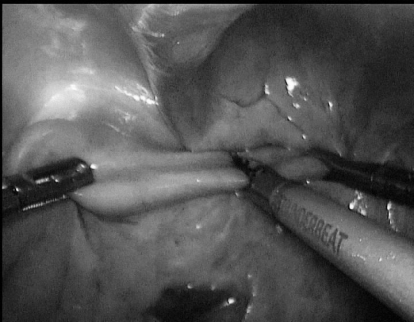

术中

▲ 图1 切开侧后腹膜,游离双侧输尿管